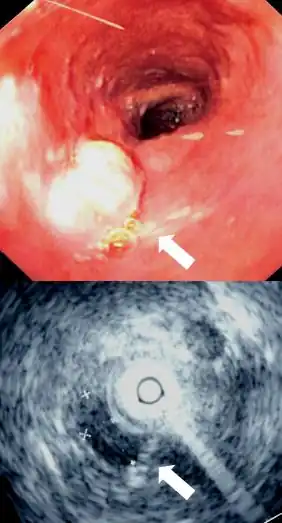

Endoscopy and radial endoscopic ultrasound images of submucosal tumour in mid-esophagus. The submucosa is seen as a dark ring on the ultrasound image. | |

Identification of the submucosa plays an important role in diagnostic and therapeutic endoscopy, where special fibre-optic cameras are used to perform procedures on the gastrointestinal tract. Abnormalities of the submucosa, such as gastrointestinal stromal tumors, usually show integrity of the mucosal surface.

The submucosa is also identified in endoscopic ultrasound to identify the depth of tumours and to identify other abnormalities. An injection of dye, saline, or epinephrine into the submucosa is imperative in the safe removal of certain polyps.